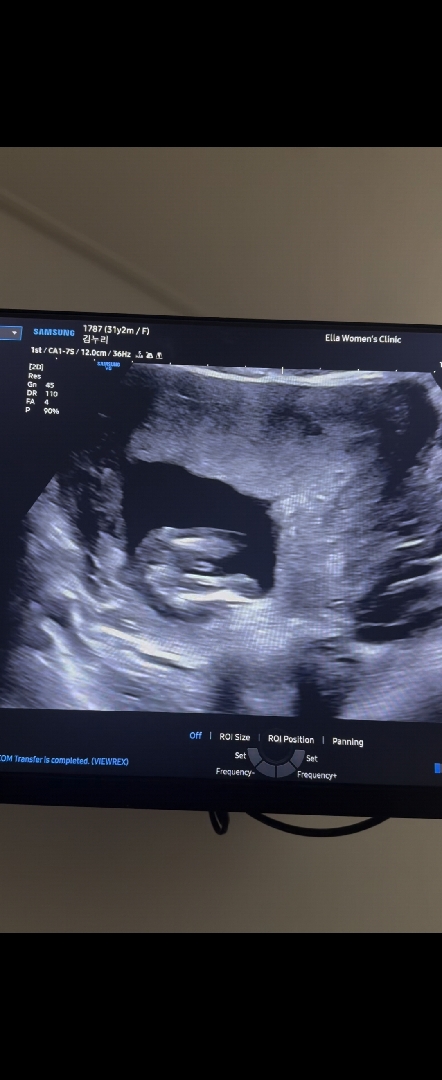

다리사이 봐주세요 ㅠㅠ

14주 이구요 애기가 앉아있어서 옆모습으로는 못봤어요 ㅠㅠ 의사선생님이 확실히는 모르겠다고 16주에 다시 보라고 하셨는데 다리사이에 저거 뭘까요 ㅠㅠ 다리사이 볼수있는 찐고수님들 투표부탁드립니다

고추냐 탯줄이냐..